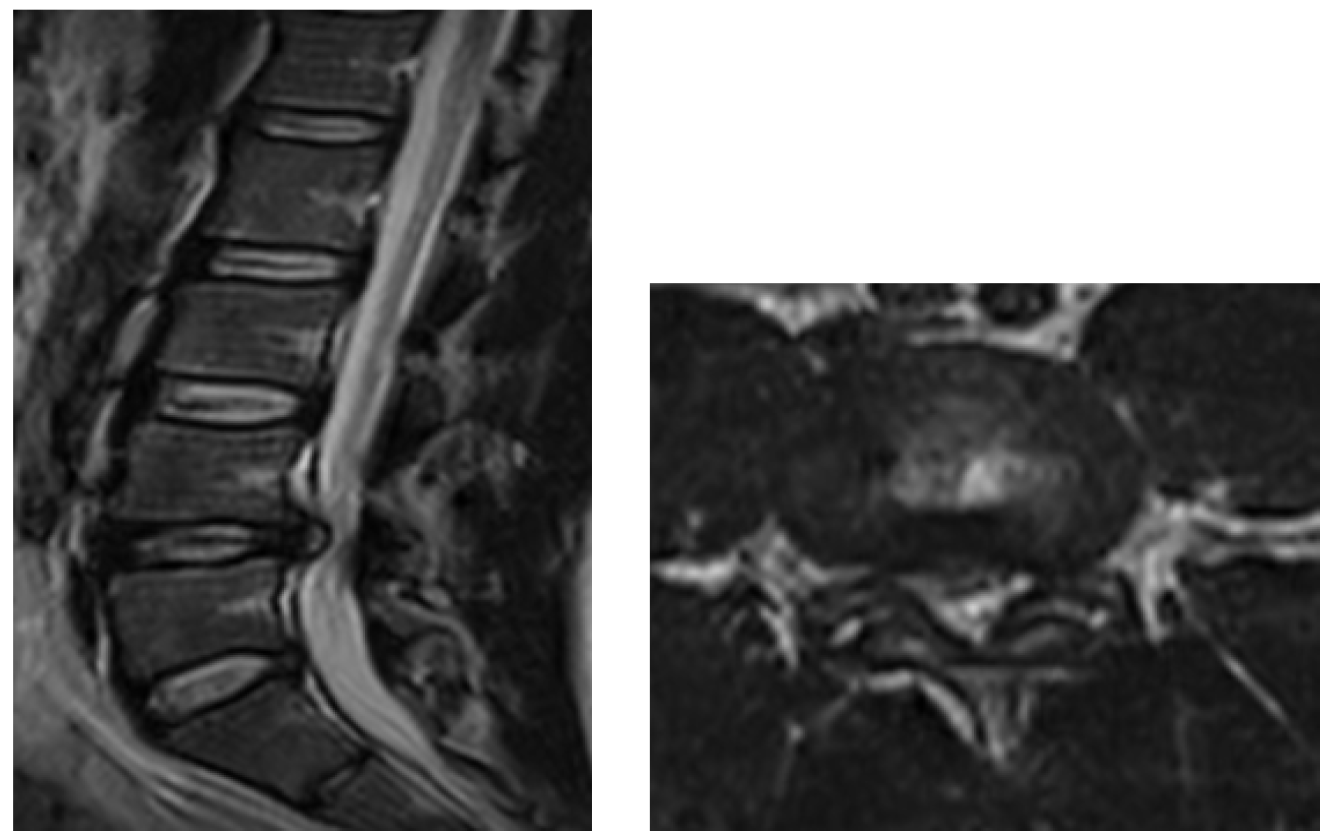

The definition of giant Lumbar Disc Herniation (GLDH) varies among different authors. It includes a herniation affecting more than 8mm, 33%, 40%, 50%, or 75% of the sagittal diameter of the spinal canal, or herniation causing complete spinal canal stenosis [3,10,11]. Our study defined GLDH as a herniated disc that affects more than 50% of the sagittal diameter of the spinal canal (Figure 1,2). Giant lumbar disc herniations are rare than more minor herniations [1]. Therefore, the incidence of GLDH in our study (4.3%) is inferior to the incidence in the literature: 8 to 22% [1,11-13].

Figure 1: T2-WI Lumbar MRI. Sagittal (Left) and axial (Right) Showing Giant Central Lumbar Disc Herniation at L4L5 Level